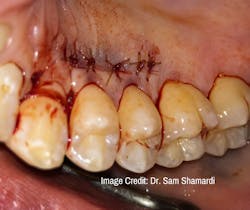

Dr. Sam Shamardi: Connective tissue grafting is a gold-standard technique for root coverage. Harvesting tissue from a donor site provides ideal tissue match, and studies show long-term stability to be superior to alternative methods such as membranes or alloderm. The donor site tissue completely regenerates and could have a new graft harvested after six weeks of healing.

Dr. Sam Shamardi: Part of the benefit of using connective tissue opposed to alternative materials is that the graft does not need to be fully covered in order to heal; partial exposure can still result in excellent results as long as the majority (at least 2/3) of the graft is covered and receives blood supply. This provides further flexibility in comparison to alloderm, where even a slight amount of exposure at any point could result in failure.